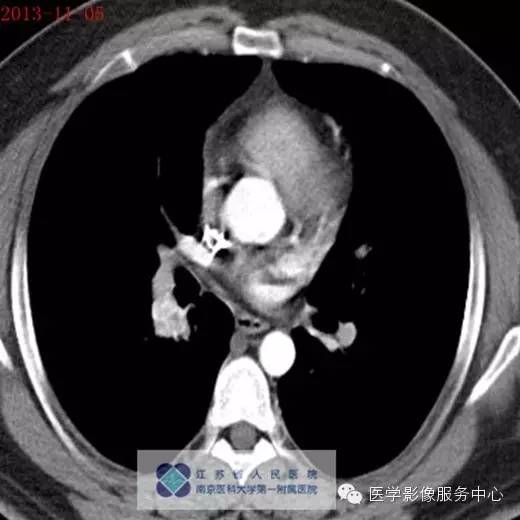

男, 26岁,因“咯血二十余日”入院 。患者一年余前无明显诱因下咯血,鲜红色,自诉无其他不适,至当地医院治疗后缓解,二十余日前无明显诱因下咯血,鲜红色,自诉无伴随症状。

2013年11月5号

影像分析:右侧肺门处见小团块状密度增高影,密度尚均匀,边缘毛糙,增强扫描病灶不均匀强化。

病理:肺神经内分泌瘤